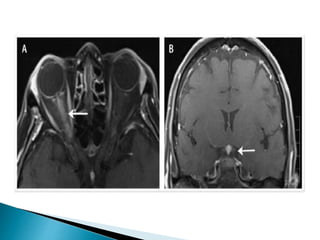

 Optic nerve can be infiltrated in systemic

malignancies such as lymphoma, leukemia, multiple

myeloma, and carcinoma

 Optic disc can be swollen or normal in appearance.

 MRI of brain and orbit may show meningeal and optic

nerve enhancement.

 Spinal tap recommended in suspected CNS

malignancy but more than one spinal tap may be

needed to detect malignant cells

 In case of localized optic nerve infiltration with no

evidence of systemic disease, histopathological

diagnosis by direct optic nerve sheath biopsy